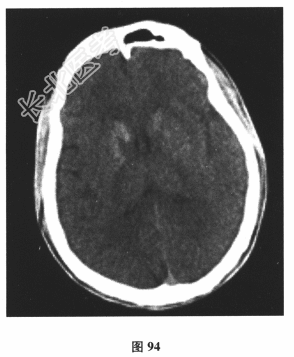

- [材料题] 患者男,24岁。由于“反复发作性四肢抽搐3个月,言语困难1d”到院就诊。3个月前饮酒后出现四肢抽搐、意识丧失,持续3min左右自行缓解;10d前再发一次四肢抽搐。遂行颅脑CT(图94)及MRI平扫检查(图95)后予丙戊酸钠对症治疗。1d前再发四肢抽搐,出现言语困难。其母亲有糖尿病病史。查体:身材矮小,意识清楚,感觉性失语,四肢肌力、肌张力正常,腱反射对称活跃,深、浅感觉正常,病理反射未引出,脑膜刺激征(-)。脑脊液:压力110mmH₂O,细胞、蛋白、葡萄糖、氯化物均正常,乳酸3.6mmol/L↑。